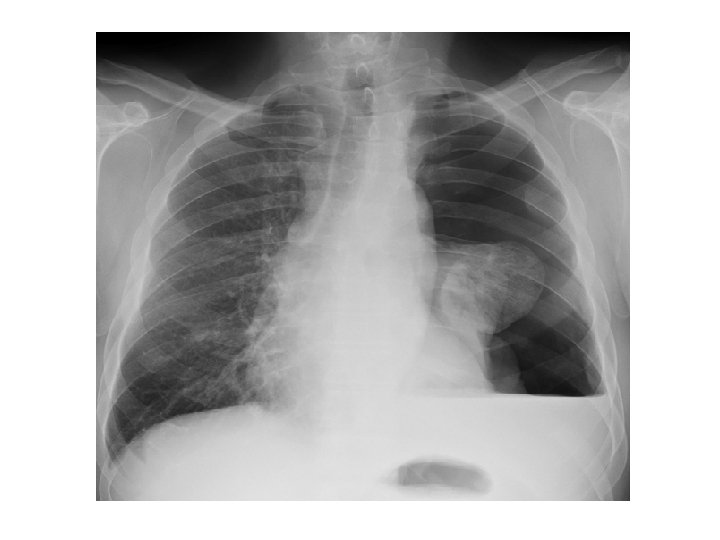

4) Pyopneumokyste : stade à la fois clinique et radiologique Clinique= signes fonctionnels et signes généraux Radiologique= images hydroaériques - Rarement à niveau rectiligne de l’abcès du poumon - Image de membrane ondulée plus fréquemment - Ainsi qu’image en nénuphar ou en coucher de soleil - Exceptionnellement image en double arc d’Ivassinévitch